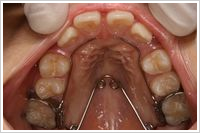

▼下顎の床矯正症例(6歳9ヶ月 男の子 主訴:下の前歯がガタガタ)

治療期間:1年2ヶ月 治療費用:¥384,000(税別)

副作用・リスク:拡大ネジを回した時に歯ぐきが痛くなることがある

下あごの前歯4本が生えてきましたが、スペース不足のためガタガタになっています。下あごに床矯正装置を装着して歯列弓を拡大していきました。8ヶ月後にはかなり歯列が良くなり、2個目の床矯正装置に交換しました。1年2ヶ月後には歯列が整ったので矯正治療を終了しました。時々装置がきっちりと装着できなくなったのですが、拡大スクリューを自分で調整することで問題なく治療を進めることができました。家でだけ装置を装着するので日頃の学校生活には全く影響がありませんでした。